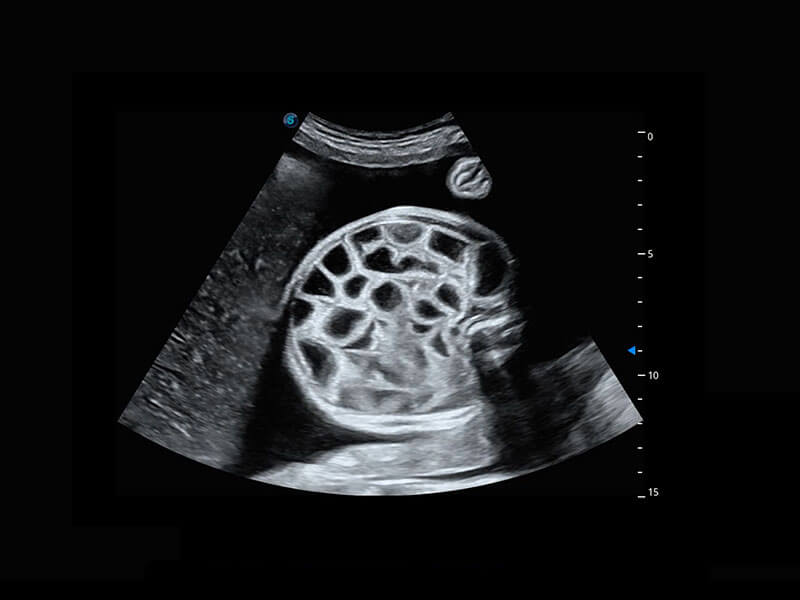

P60搭载一系列胎儿心脏成像技术,实现精细的胎儿心脏评估。

四腔切面

胎心容积成像